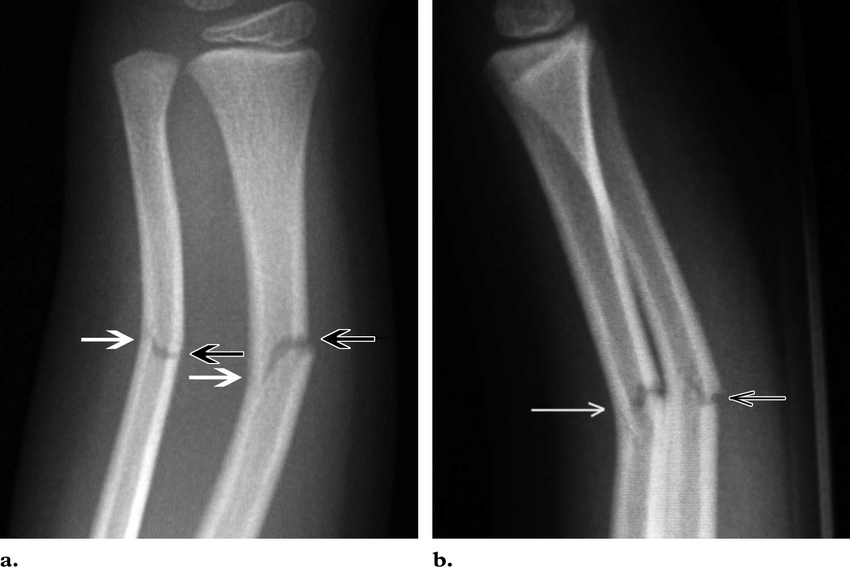

Greenstick fracture - Definition

The bone bends rather than breaks (similar to that of a green tree branch)

Greenstick fracture - Cause

Occurs most often in children in bones that have not completely ossified and still contain cartilage